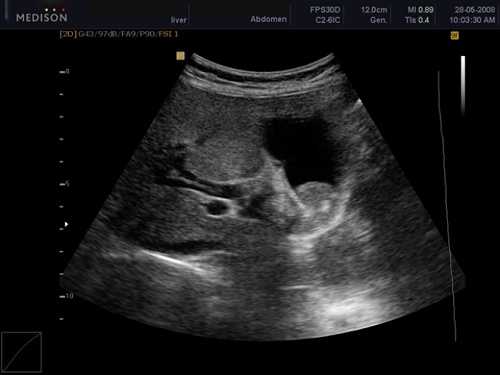

- Спленомегалия. УЗИ сканограмма

- Спленомегалия при портальной гипертензии. УЗИ сканограмма

- Кисты селезенки. УЗИ сканограмма